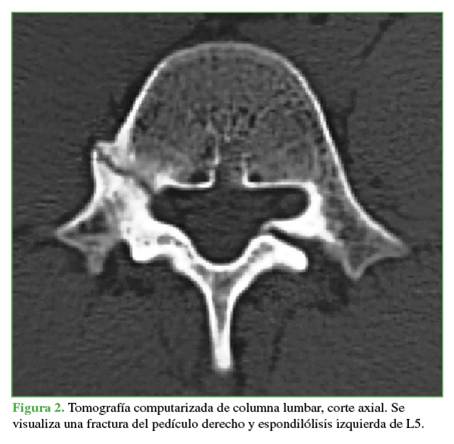

Se tomaron radiografías de columna lumbar, de frente, de perfil y oblicuas que revelaron esclerosis del pedículo derecho y espondilólisis izquierda de L5. La tomografía computarizada mostró, además de la lesión antes descrita, una solución de continuidad en el pedículo derecho, con márgenes escleróticos e hipertróficos (Figuras 1 y 2). En la resonancia magnética, se visualizó un edema en dicho pedículo lumbar (Figuras 3 y 4).

Un rasgo habitual en la pediculólisis es la esclerosis del pedículo, pero aún no resulta claro si esto representa un fenómeno de adaptación anterior a la fractura o si es una consecuencia de ella.9 Esta esclerosis unilateral le da el aspecto de vértebra anisocórica en la imagen radiológica. Sin dudas, la tomografía computarizada permite evaluar mejor el cuadro, realizar diagnósticos diferenciales, controlar la evolución y, en algunos casos, efectuar una planificación terapéutica. Las características suelen ser la presencia de solución de continuidad radiolúcida con márgenes escleróticos e hipertróficos.4 La resonancia magnética tiene una elevada sensibilidad a la hora de diagnosticar este tipo de lesiones que, si bien puede mostrar o no el trazo de fractura a nivel del pedículo, sí manifiesta el edema